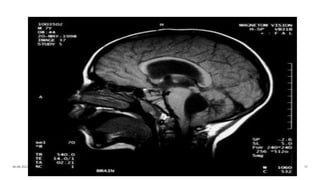

Anatomy of brain

06-08-2021 4

Anatomy of ventricles